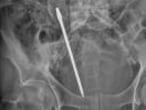

El pincho le entró por la mejilla a la altura de la nariz y le salió por la nuca, pero no le tocó los ojos, ni la médula espinal ni ningún vaso sanguíneo, según detalla el diario The Kansas City Star. Koji Ebersole, director de neurocirugía endovascular en el Hospital de la Universidad de Kansas, donde se le sometió a una operación de alto riesgo para extraer el utensilio el pasado fin de semana, explica al diario que en "uno entre un millón de casos" un objeto punzante penetra "13 o 15 centímetros por la cara hasta la parte trasera [de la cabeza] y no toca" ningún punto clave.

La forma del pincho, según los médicos, añadía una dosis extra de peligro a la operación, ya que no era redondo como la mayoría sino cuadrado y con bordes afilados. Tenía que salir completamente recto, tan limpiamente como había entrado, ya que torcerlo podía causar lesiones severas, posiblemente mortales.